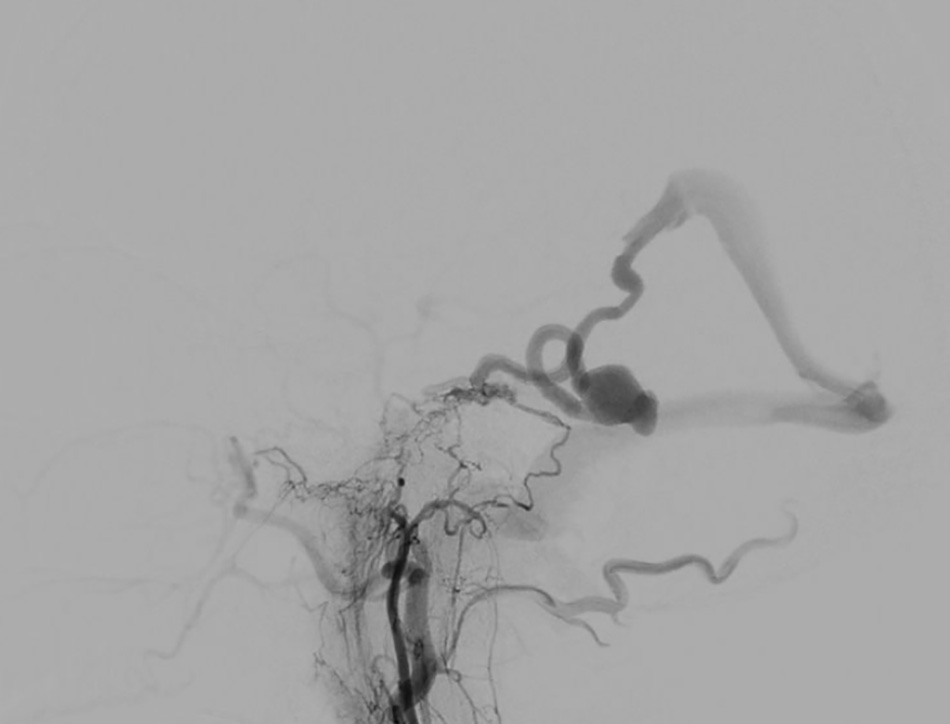

The doctors at FV Hospital’s Accident & Emergency Department swiftly conducted tests to assess the patient’s condition. An MRI scan revealed bleeding in the brainstem. Since the brain haemorrhage was not caused by trauma or impact, a follow-up CT scan confirmed a rare diagnosis: a dural arteriovenous fistula with a large 25mm venous aneurysm that had ruptured. Immediate intervention was critical, as the patient’s life was at imminent risk.

The brain vascular images of the patient were considered very “unusual,” showing a large venous aneurysm that had ruptured.

Without hesitation, the multidisciplinary medical team, including the Accident & Emergency, Anaesthesiology & ICU, and Imaging & Interventional Radiology departments, held an urgent consultation. Dr Huynh Huu Danh, Specialist Level I and expert in Imaging and Interventional Radiology at FV Hospital, assessed the case as a rare dural arteriovenous fistula with a large ruptured venous aneurysm, posing a risk of continued bleeding and a serious threat to the patient’s life.